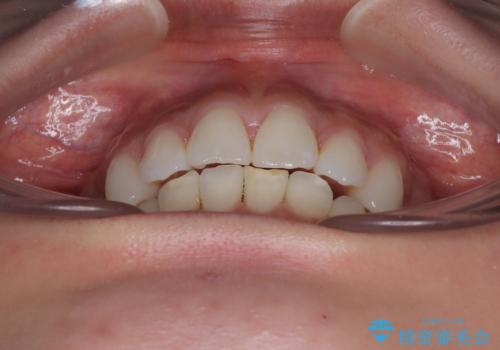

- 口元の突出感を気にして来院された患者様です。

左右ともに奥歯の咬み合わせに問題があり、上顎臼歯が前方位にある状態で、結果として上顎前歯全体が前方位かつ叢生になっていました。